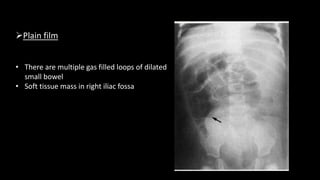

Plain film

• There are multiple gas filled loops of dilated

small bowel

• Soft tissue mass in right iliac fossa